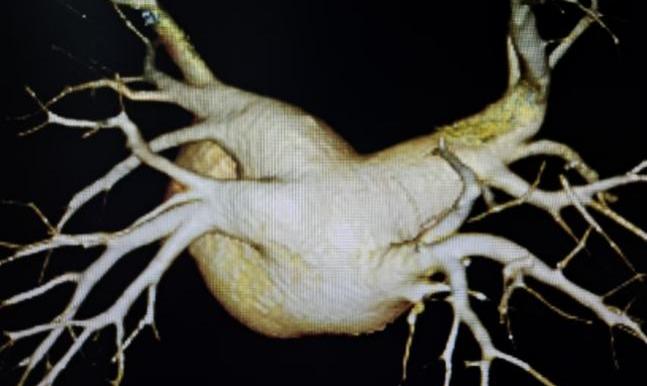

周某,78岁,长期受到持续性房颤的困扰,合并冠心病、高血压,并有一次卒中史,病程长达十余年。起初,症状表现为偶发的心悸和胸闷,但近几年症状逐渐加重,发展为频繁气短、乏力,严重影响了日常生活。考虑到他的卒中史以及房颤带来的潜在风险,且曾因心脏功能异常植入过起搏器,周爷爷的治疗方案在兰州大学第一医院心血管团队的精心制定下,采取了个性化的综合治疗方案,不仅通过先进的脉冲消融术精准处理房颤,还结合其卒中风险高的特点,施行了经皮左心耳封堵术,从源头预防卒中发生,为患者提供全方位保护。这一双管齐下的治疗策略,不仅显著改善了心律失常,还为患者的未来健康筑起了一道坚实的屏障。

FARAPULSE导管花瓣消融

左心耳封堵器完美封堵